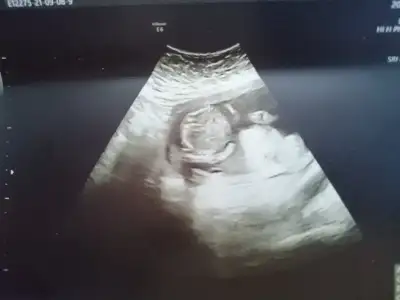

dr soylemeden siz gorun genital nub teorisi ( bebegin cinsiyeti)

14 haftaligiz tahmin alabilirmiyim